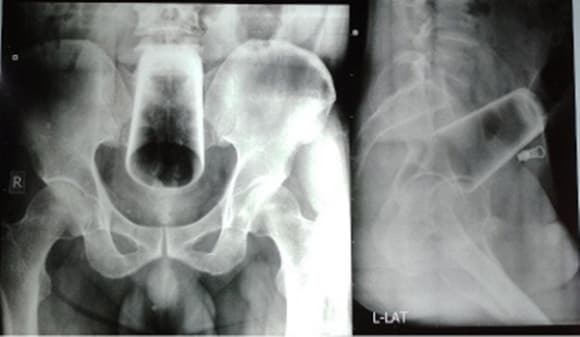

남성은 변비로 인한 극심한 고통을 호소했지만 의료진은 남성에게서 별다른 외상을 찾을 수 없었다. 복부가 부어있는 상태도 아니었으며 항문에도 상처나 출혈이 없어 의료진은 엑스레이 촬영을 실시했다. 그 결과 남성의 복부 한가운데서 12㎝의 유리컵이 발견됐다.

의료진은 항문을 통해 유리컵을 빼내려고 시도했으나 유리컵이 뒤집혀 있는 데다 깨질 위험이 높아 결장절개술로 유리컵을 제거했다.